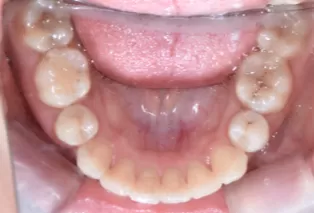

Photos intra-orales